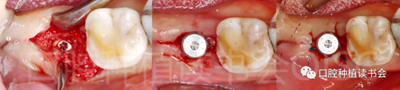

5.3.1 使用球鉆及帶有定深器的先鋒鉆在根分叉上方定點(diǎn)、定深,確定方向(圖14)。

圖14 選擇在殘根根分叉上方定點(diǎn),先鋒鉆預(yù)備方向。

5.3.2 逐級預(yù)備種植窩洞后,側(cè)切鉆分根,微創(chuàng)拔除殘根,探查頰、舌側(cè)骨板完整,仔細(xì)搔刮拔牙窩,生理鹽水沖洗(圖15)。

圖15 微創(chuàng)拔牙后確認(rèn)種植窩洞位于牙槽間隔內(nèi)。

5.3.3 根據(jù)拔牙窩內(nèi)的牙槽間隔高度,植入康盛CANSUN柱形親水種植體(4.3*8mm),確保種植體肩臺與牙槽間隔平齊,種植體的所有表面均被自體骨包繞(圖16),植入扭矩為25N.cm。

圖16 盡量讓種植體表面被牙槽間隔的自體骨包繞。

5.3.4 旋入覆蓋螺絲,在種植體與四周骨壁的間隙內(nèi)植入 Bio-Oss Collagen,植骨材料用生理鹽水濕潤后,用15#刀片分割為小塊分別植入,并用充填器壓實(shí)(圖17)。

圖17 后牙即刻種植植骨推薦使用骨膠原材料,有利于軟組織愈合。